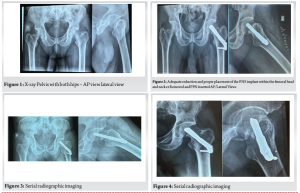

Initial radiological findings X-rays of the pelvis with both hips (AP and lateral views) revealed (Fig. 1).

A displaced intracapsular fracture of the right femoral neck.

The fracture line was transverse with a vertical orientation, categorised as a Pauwels Type III.

There was a loss of continuity with medial breaking, absence of calcar support, and no impaction.

The proximal femur showed trabecular thinning and generalised osteopenia, strongly suggesting osteoporotic bone.

No signs of pathological lesion or prior implants were observed.